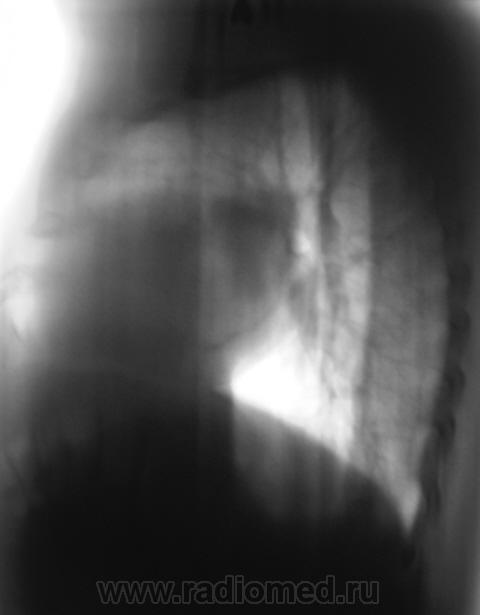

2. Конечно, мы на свой страх и риск, произвели дообследование, согласно стандарту. Итог дообследования представлен в серии 3.

СЕРИЯ 2.

СЕРИЯ 3.